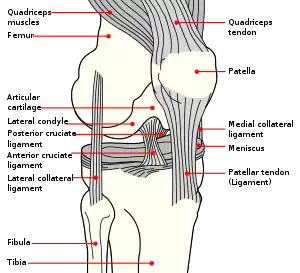

The patella (pl.: patellae or patellas), also known as the kneecap, is a flat, rounded triangular bone which articulates with the femur (thigh bone) and covers and protects the anterior articular surface of the knee joint. The patella is found in many tetrapods, such as mice, cats, birds and dogs, but not in whales, or most reptiles.

The patella is a sesamoid bone roughly triangular in shape, with the apex of the patella facing downwards. The apex is the most inferior (lowest) part of the patella. It is pointed in shape, and gives attachment to the patellar ligament.

The front and back surfaces are joined by a thin margin and towards centre by a thicker margin.[1] The tendon of the quadriceps femoris muscle attaches to the base of the patella.,[1] with the vastus intermedius muscle attaching to the base itself, and the vastus lateralis and vastus medialis are attached to outer lateral and medial borders of patella respectively.

The upper third of the front of the patella is coarse, flattened, and rough, and serves for the attachment of the tendon of the quadriceps and often has exostoses. The middle third has numerous vascular canaliculi. The lower third culminates in the apex which serves as the origin of the patellar ligament.[1] The posterior surface is divided into two parts.[1]

The upper three-quarters of the patella articulates with the femur and is subdivided into a medial and a lateral facet by a vertical ledge which varies in shape.

In the adult the articular surface is about 12 cm2 (1.9 sq in) and covered by cartilage, which can reach a maximal thickness of 6 mm (0.24 in) in the centre at about 30 years of age. Owing to the great stress on the patellofemoral joint during resisted knee flexion, the articular cartilage of the patella is among the thickest in the human body.

The lower part of the posterior surface has vascular canaliculi filled and is filled by fatty tissue, the infrapatellar fat pad.

The primary functional role of the patella is knee extension. The patella increases the leverage that the quadriceps tendon can exert on the femur by increasing the angle at which it acts.

The patella is attached to the tendon of the quadriceps femoris muscle, which contracts to extend/straighten the knee. The patella is stabilized by the insertion of the horizontal fibres of vastus medialis and by the prominence of the lateral femoral condyle, which discourages lateral dislocation during flexion. The retinacular fibres of the patella also stabilize it during exercise.